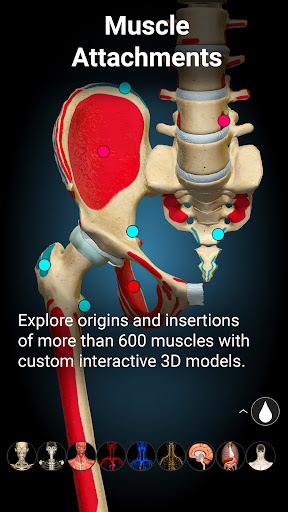

★ Muscles